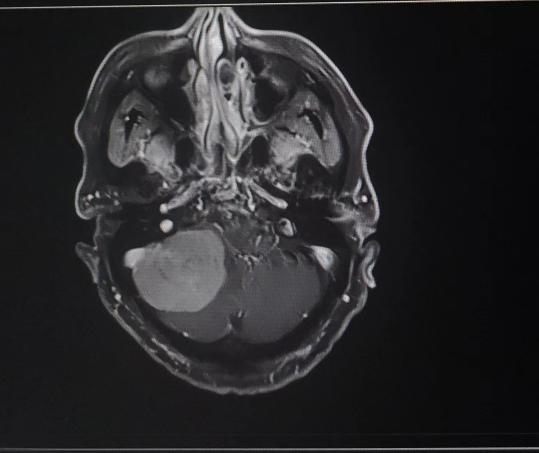

患者入院后,头颅MR检查后发现,小脑右侧长了巨大肿瘤,直径约6公分,患者家属收到不小的惊吓。患者4年前曾做过一次头颅核磁共振,当时肿瘤较小,考虑到患者已经88岁,家人还是决定保守观察,没想到如今,它已经长大到足足有一个土豆那么大,而且患者头晕较重,反复恶心、呕吐,卧床不起,因此必须进行手术,才能解决患者病症。

患者家属反复考虑、综合思量后,决定接受手术治疗。神经外科二病区主任白西民及团队进行综合评估,术前讨论,研究患者肿瘤位置、毗邻关系及心肺状况,制定周密手术方案。联合呼吸科、心内科、麻醉科及重症医学科等学科会诊,研究制定详细手术方案及应急预案。